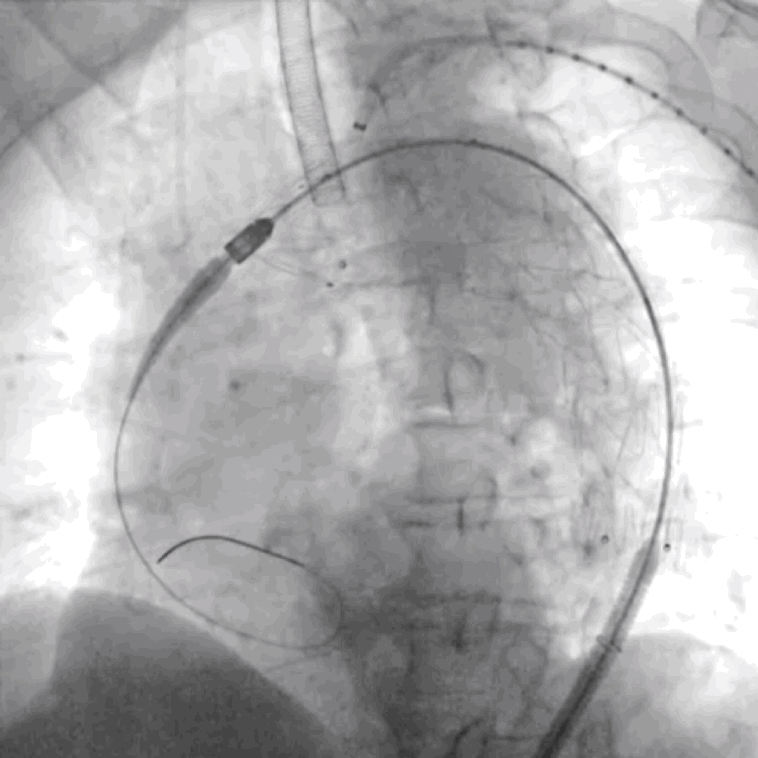

4. 依次导入球囊3mm*30mm、6mm*40mm至开窗口行扩张并再次确认导丝头穿过主动脉支架覆膜。

泥鳅导丝怎么用符伟国/王利新教授团队:0.035"普通泥鳅导丝进行胸主动脉弓上分支原位开窗的病例分享_https://www.jmylbn.com_新闻资讯_第17张

使用3mm*30mm球囊扩张窗口,改变DSA角度证实破膜成功

泥鳅导丝怎么用符伟国/王利新教授团队:0.035"普通泥鳅导丝进行胸主动脉弓上分支原位开窗的病例分享_https://www.jmylbn.com_新闻资讯_第18张

进一步使用6mm*40mm球囊扩张开窗口